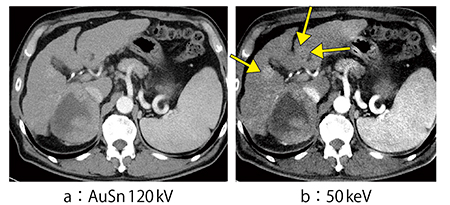

症例3は,肺動脈血栓塞栓症疑い症例である。高齢で腎機能が低下していたため,造影剤は240mgI/mLを100mL投与し肺と下肢の造影CTを施行した。AuSn120kV画像では,肺と下肢のいずれも血栓は不明瞭であるが,50keV画像では,特にコロナル画像において明瞭に肺動脈の血栓を指摘可能であり(図4),下肢についても血栓がはっきりと黒く抜けているのが確認できる(図5)。

図4 症例3:肺動脈血栓塞栓症疑い症例